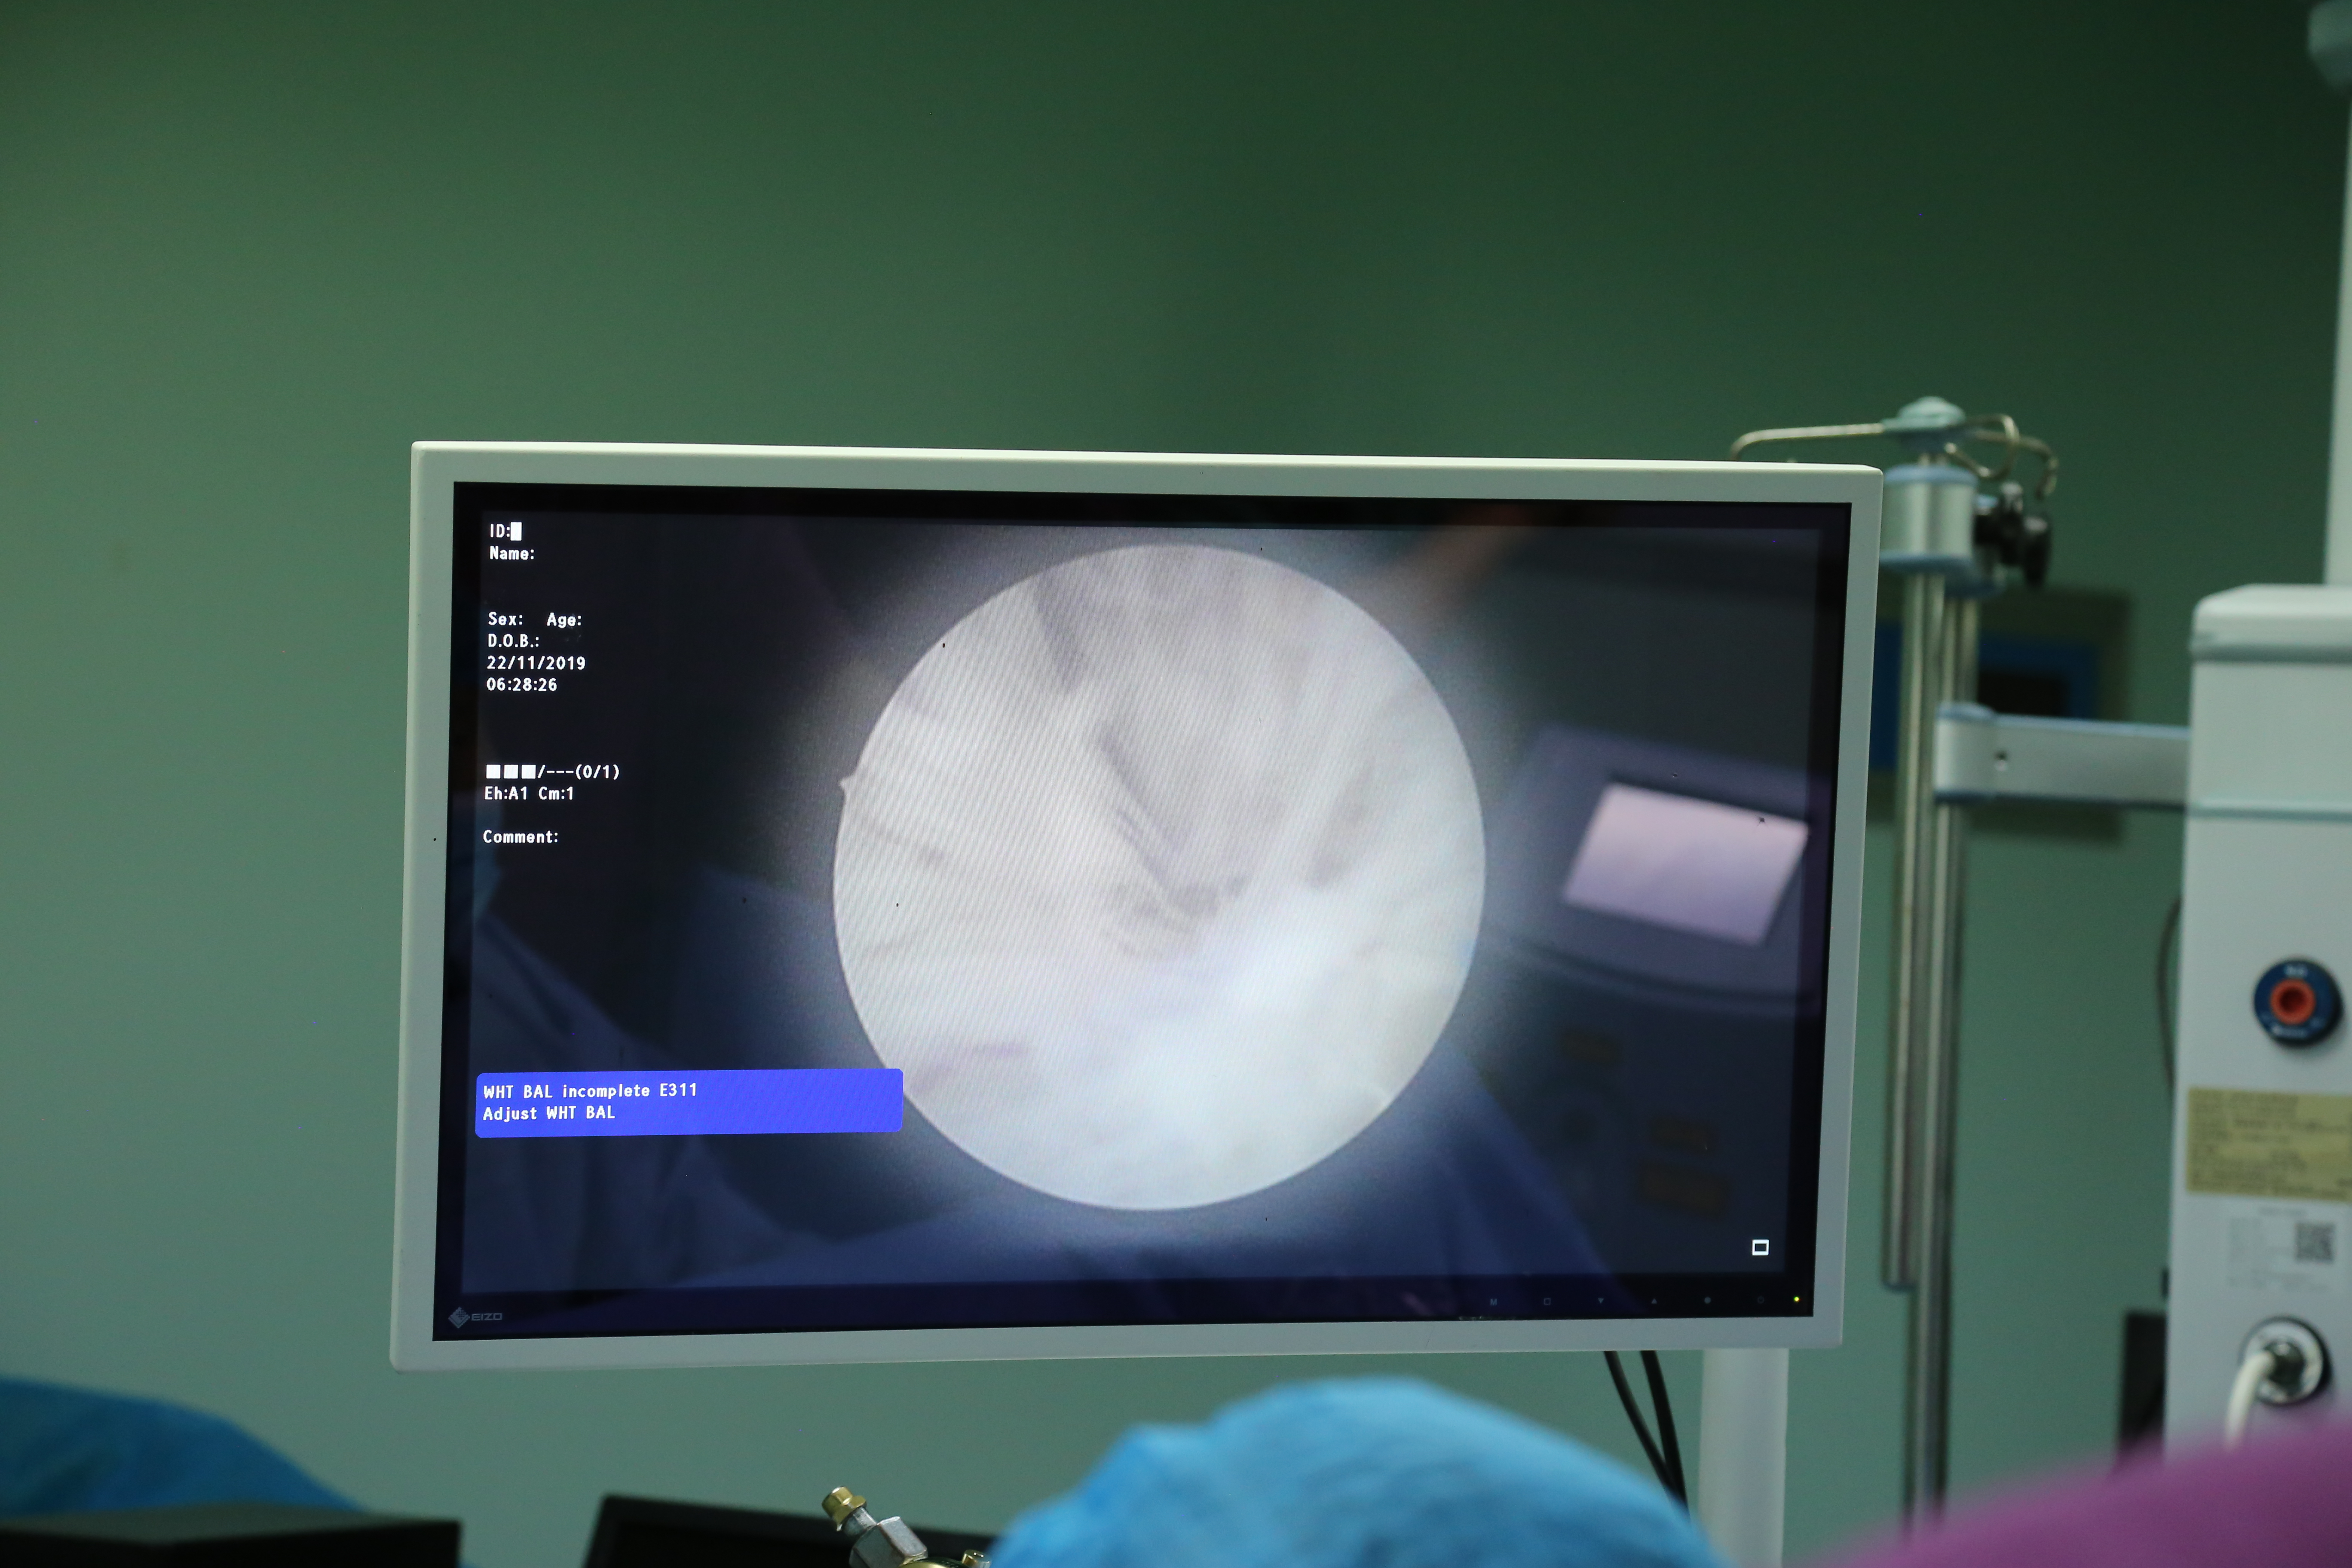

11月22日,我院综合外科成功开展了我区首例经尿道钬激光前列腺剜除术+前列腺组织粉碎术,目前病人病情平稳,恢复良好。此例手术的成功开展,标志着医院在前列腺增生的微创治疗方面取得了新的突破。

在麻醉手术室医护人员的密切配合及省立三院专家的指导下,手术中利用钬激光独特的微爆震效应和最浅的组织穿透深度,在前列腺增生腺体与外科包膜的平面中精细分离,直至整体切除前列腺送入膀胱,应用“龙卷风”组织粉碎器将前列腺粉碎吸出膀胱。该手术方式类似于前列腺开放手术时用食指抠除前列腺,与开放手术效果相通,且较经尿道前列腺电切手术出血更少、更加微创,恢复更快。术后患者恢复良好,术后1天停膀胱冲洗,术后2天进行膀胱功能锻炼,术后3天拔出尿管,术后第4天患者排尿通畅,康复出院。